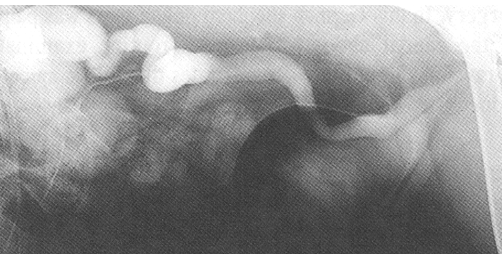

What is being shown here after the use of Intravenous Urography?

Ectopic ureter —> the ureter is dilated and is inserting into the urethra rather than the trigone of the bladder